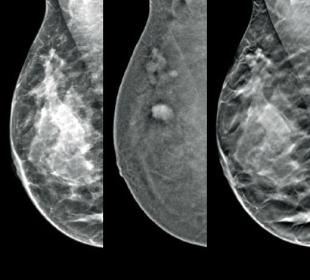

Screening & Diagnosis